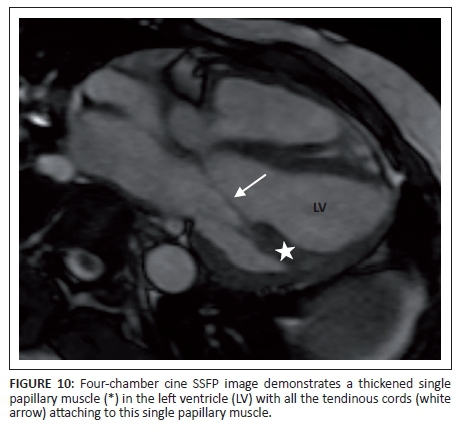

There is considerable variation in the number of tendinous cords normally seen attaching to each of the five papillary muscles, with an average of 12 tendinous cords per papillary muscle. The individual papillary muscles are normally the same thickness as the normal left ventricular myocardium.

The most common congenital abnormality of the papillary muscles is a single papillary muscle to which all the tendinous cords of the mitral valve attach (Figure 10), resulting in a 'parachute' mitral valve.9